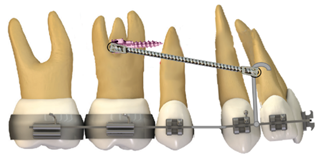

Figura 3. Cierre de espacio y tracción anterior.

Elaboración: Los autores.

Camuflaje con extracción de primeros premolares superiores y retracción en masa del bucle en T.

Para esta técnica se realiza la extracción de los primeros premolares superiores con una retracción en masa directamente de los 6 dientes anteriores mediante un retractor canino en T (figura 4), activando gradualmente cada mes de 1-2 mm para el cierre del espacio del diente extraído, consiguiendo una Clase I canina y Clase II molar, debido a que es una técnica con anclaje recíproco 15.